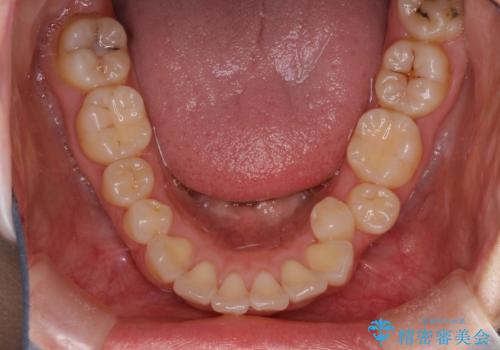

抜歯をして前歯を下げ、ガタつきを取り除く ワイヤー矯正

- 上顎両側第1小臼歯、下顎左側第2小臼歯の3本を抜歯、ラビアルのワイヤー矯正を計画した。